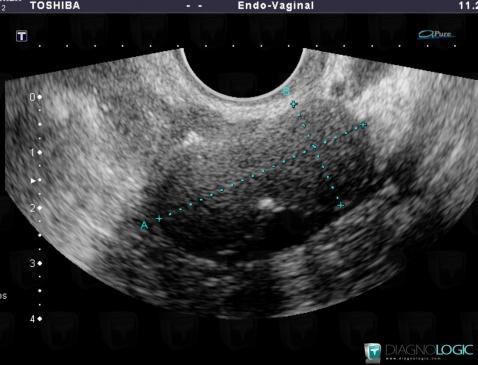

Fibrothécome , Annexe / Ovaire - trompe, Pelvis / Périnée, Echographie

Voici les informations spécifiques à l'image clé ci dessus:

- Diagnostic Fibrothécome , Localisation(s) Annexe / Ovaire - trompe, comportant les gammes Masse annexielle solidePelvis / Périnée, comportant les gammes Masse pelvienne solide